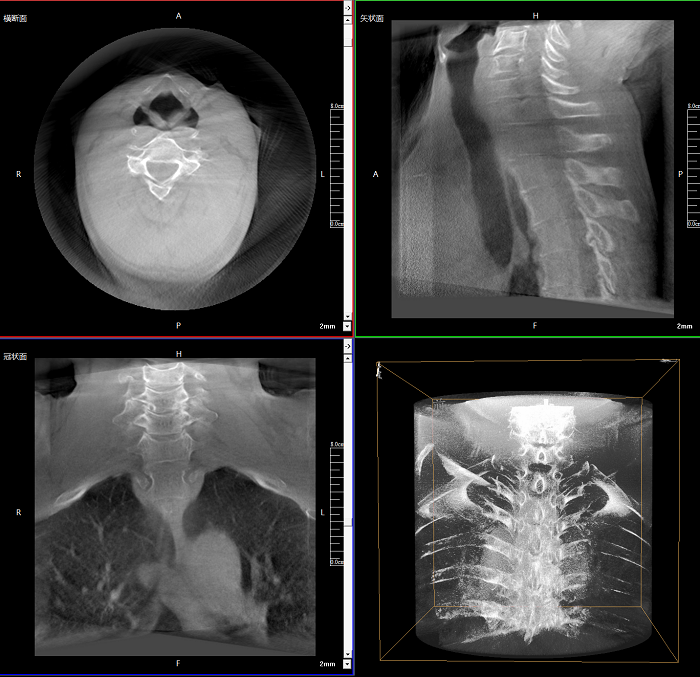

三維成像 全面觀(guān)察

任意視角、任意切面觀(guān)察

術(shù)中實(shí)時(shí)生成橫斷面、矢狀面、冠狀面及三維影像,可在任意切面、任意角度評估植入物和解剖結構的相對位置。

術(shù)中CT檢查 減少翻修概率

通過(guò)術(shù)中三維影像的檢查,可以立即發(fā)現植入物的錯位,減少不必要的第二次手術(shù),減少并發(fā)癥概率以及感染風(fēng)險。

較9英寸常規平板視野提升100%,幫助醫生迅速判斷椎體節段,定位手術(shù)部位。

400萬(wàn)像素成像

易于觀(guān)察細微病灶,利于胸部、腹部、脊柱關(guān)節等復雜骨骼和軟組織的成像。

Clinical picture

臨床圖片